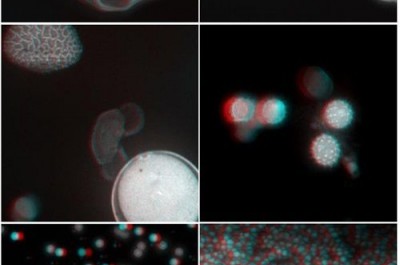

西安光機所成功研製激光掃描實時立體顯微鏡

據中國科學院網站消息,日前,中國科學院西安光學精密機械研究所瞬態光學與(yu) 光子技術國家重點實驗室(簡稱:瞬態室)超分辨成像團...